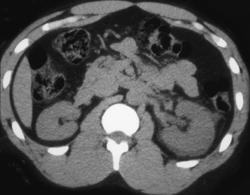

Acute Pyelonephritis